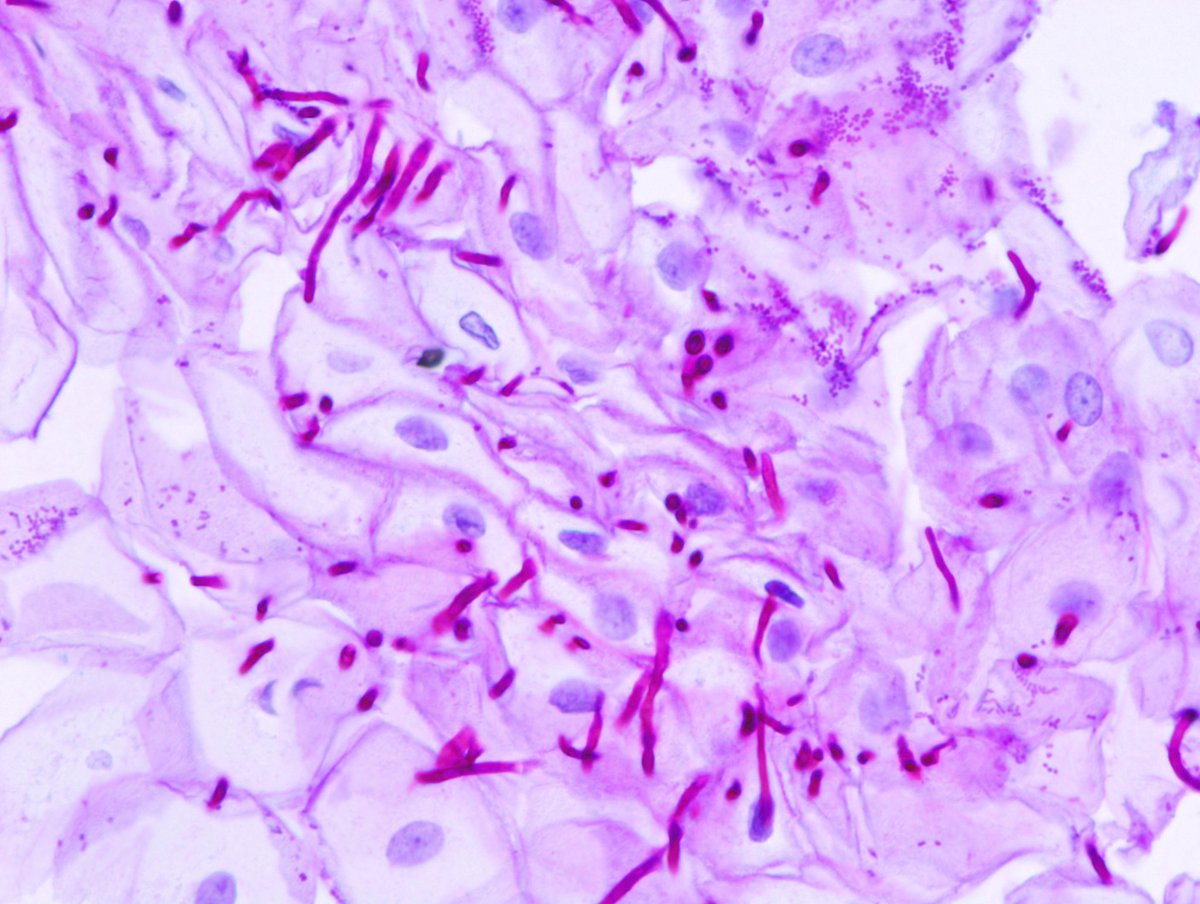

📌Giemsa

📌Crystal violet acetate

هذي الاثنين تستخدم للكشف عن بكتيريا ال

H. Pylori

وتظهر فيها باللون الازرق

والانسجة المحيطة بتدرجات الازرق 🧿👀

📌 DIFF QUICK

وتستهدف بكتيريا ال H. PYLORI

والي تظهر باللون الازرق الغامق